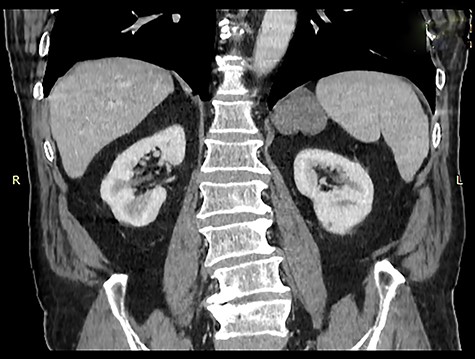

An asymptomatic 75-year-old Caucasian male was referred to our institution for the evaluation of an incidental left adrenal mass pointed out on computed tomography (CT) scan at medical checkup. The patient had a past medical history of hypertension and benign prostatic hyperplasia. The medication list included perindopril, indapamide, bisoprolol and tamsulosin. He had no previous surgeries and his family history was unremarkable. Physical examination was normal. Abdominal contrast-enhanced CT scan revealed a 5.6 × 3.5 × 3 cm, solid, nodular, hypodense mass that was thought to be arising from the left adrenal gland, suggesting an adenoma (Figs 1 and 2).

Coronal image of contrast enhanced computed tomography of abdomen and pelvis showing a hypodense mass in the region of the left adrenal gland, medial to the spleen and above the kidney.